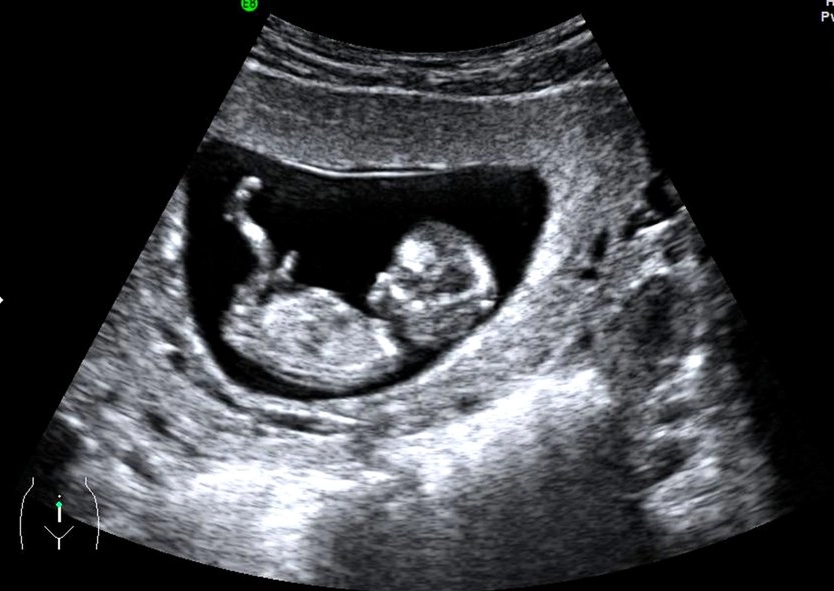

Forget the month debate. The 12-week scan is where the magic—and the medicine—happens. This is often the first detailed look at your baby, and the emotional impact is huge. It's not just a blurry blob anymore.

The "Wow" Factor: What You'll Actually See

While the tech is taking measurements, you'll get to watch. At 12 weeks, your baby looks undeniably human.

| Arms and legs with tiny hands and feet | Your baby is moving, maybe even waving or kicking, though you might not feel it yet. |

| A flickering heartbeat | The heart is fully formed and beating between 120-160 beats per minute. They'll measure this. |

| The nasal bone | The presence of a visible nasal bone is another soft marker screened for. |

| The stomach and bladder | They're starting to function! The baby swallows amniotic fluid. |

You might also get confirmation if you're having twins (or more!). This scan checks for separate amniotic sacs and placentas, which is vital information for your care.